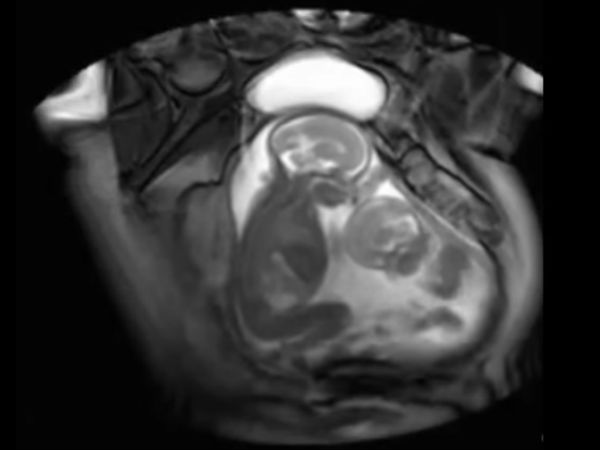

Adorable Video Of Twins Fighting In Womb!

These twins are going to be little brats, as we can see them fight in their mother's womb! Check out the crazy video and decide...

Being pregnant is a great feeling, and being pregnant with twins is even more a greater feeling along with a big responsibility. Imagine a day you walk into the clinic for a regular checkup and all that you see is that your unborn twins are having a cute little fight in the womb!

This is something very rare that was captured on camera! A doctor was using a new technology as part of a London medical study where she examined a pregnant woman and scanned to find out that the twins were actually having a cute little fight inside the womb.

The new technology that the doctor had used in this case is called cine-MRI scan; and this is done to study twin-to-twin transfusion syndrome.

This "twin-to-twin transfusion syndrome" occurs when the twins share a placenta that contains abnormal blood vessels. This is something that can cause one of the twins to get less nutrients than the other.

In this you can see the little smaller sized twin kick the bigger twin, and it looks like he/she needs his/her own space. The elder one does not retaliate initially, but gives it back soon.

Guess all this happens when the twins share the same placenta. Most of the mothers who have seen the video can relate to their children fighting to get the best spot on the couch or get the best seat.